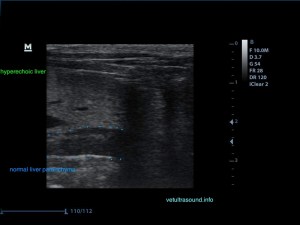

Το ήπαρ εμφανίζεται υπερηχογενές και ο ήχος εξαντλείται καθώς περνάει μέσα από αυτό. Δεν είναι εύκολη η διαφοροποίηση του τοιχώματος της πυλαίας φλέβας σε σχέση με το υπόλοιπο παρέγχυμα.